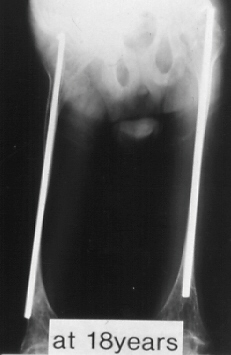

A 18-years-old boy. Body height 114cm. Sillence type III.

The first visit was at 4 years of age. He sustained 16 fractures in L/E and 30 fractures in U/E. He underwent 9 operations. He had 80 degrees progressive scoliosis and recently underwent posterior spinal fusion with internal instrumentation. He obtained his initial gate at 18 months of age, and had been practical ambulator until 9 years old. However, the diameter of the femur which was 15mm at 7 years of age had started to decrease prior to the functional aggravation. He eventually became a non-ambulator after the ankle joint fracture at 9 years old. The diameter of the right and left femur at the age of 18 were 7 and 8 mm respectively.